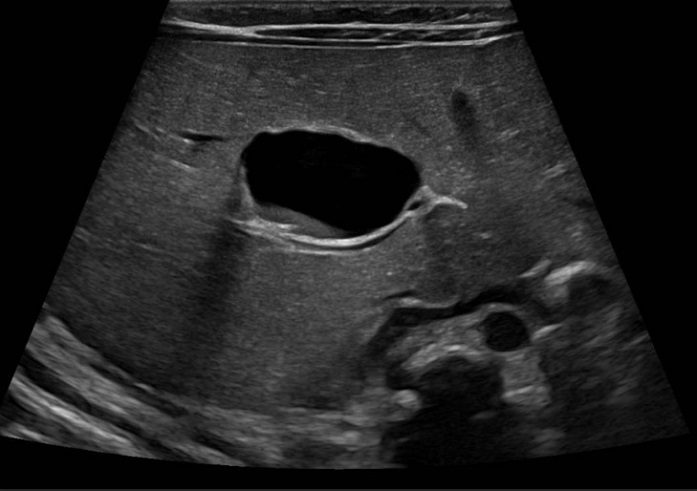

Para completar el estudio, se solicitó una analítica sanguínea, en la que no se objetivaron alteraciones en la función hepática, con albúmina, glucosa y coagulación normal, y sin colestasis ni hipertransaminasemia. La alfafetoproteína era de 150 ng/ml. A los 4 meses de vida, la ecografía de control no mostró cambios significativos con respecto a las previas (Figura 3).

| Figura 3. Quiste hepático congénito. Ecografía posnatal de control. En el segmento IV continúa visualizándose un quiste simple unilocular de pared fina, de diámetros similares al estudio previo (25 x 17 mm en sus ejes TR x AP), actualmente con un pequeño nivel ecogénico declive en su interior |